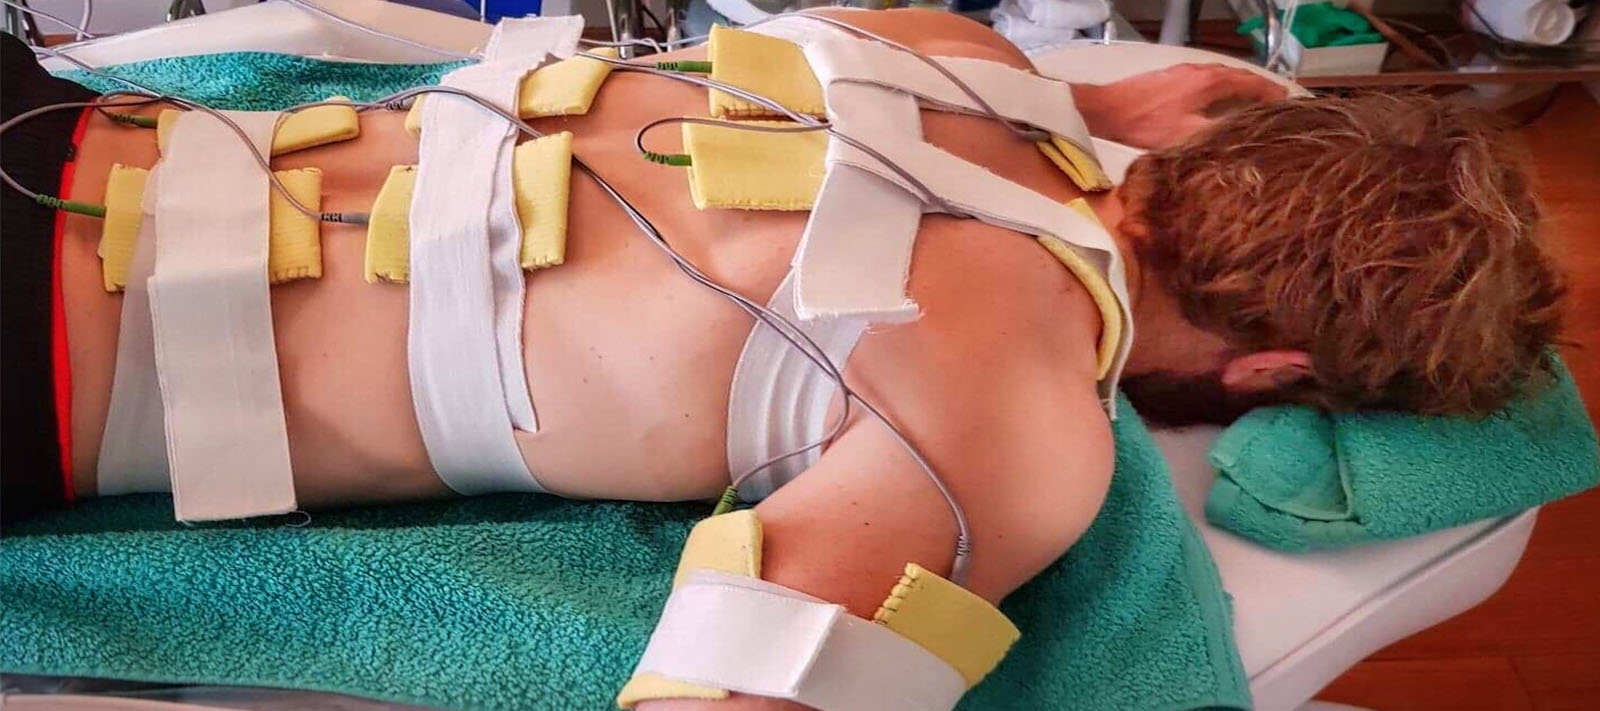

Safe and Non-Invasive Procedure designed and founded on Physical Therapy to

Very advanced and efficient method, precise and non-invasive! The procedure is completely safe, totally painless and provides highly effective results. NOT requiring anesthesia or downtime ensuring that women can resume their routine and regain their confidence soon after therapy.

The apparatus therapeutic effect is based on thermal effects enabling focused ultrasound waves to precisely target tissue and the depth NOT impairing any structures through which they travel. Transformation of HIFU waves energies into thermal energies achieves therapeutic effects which are exclusively NON-ABLATIVE and BIOSTIMULATIVE enabling the treatment to stimulateneosynthesis of collagen and its regeneration and reorganisation. It also encourages neovascularization of the treated area.

In recent years HIFU technology has been successfully applied in treatments of vaginal relaxation (VRS) and stress incontinence (SUI). Precise application of HIFU waves to vaginal walls at a depth of 3 to 4.5mm warms submucosa and mucous membrane to 65⁰C. This method practically instigates connective tissue of mucous membrane to regenerate. The treatment results in higher numbers of stronger, remodeled and narrowed collagen fibers which permeate and provide strength of vaginal walls. In addition, biostimulative effects of HIFU wave initiated regenerative processes have positive impacts on the elastic fibers of mucosa and pelvic muscles. Final results of the treatment are reflected by a narrowed vaginal canal with stronger, more resistant and healthier walls. All these effects are beneficial in the treatment of SUI hence why HIFU is also applied in treatments of first and second degree SUI whilst third degree SUI requires surgery. HIFU application in treatment of first and second degree SUI can significantly delay the development of third degree SUI and therefore delay or completely eliminate the need for surgical treatment.